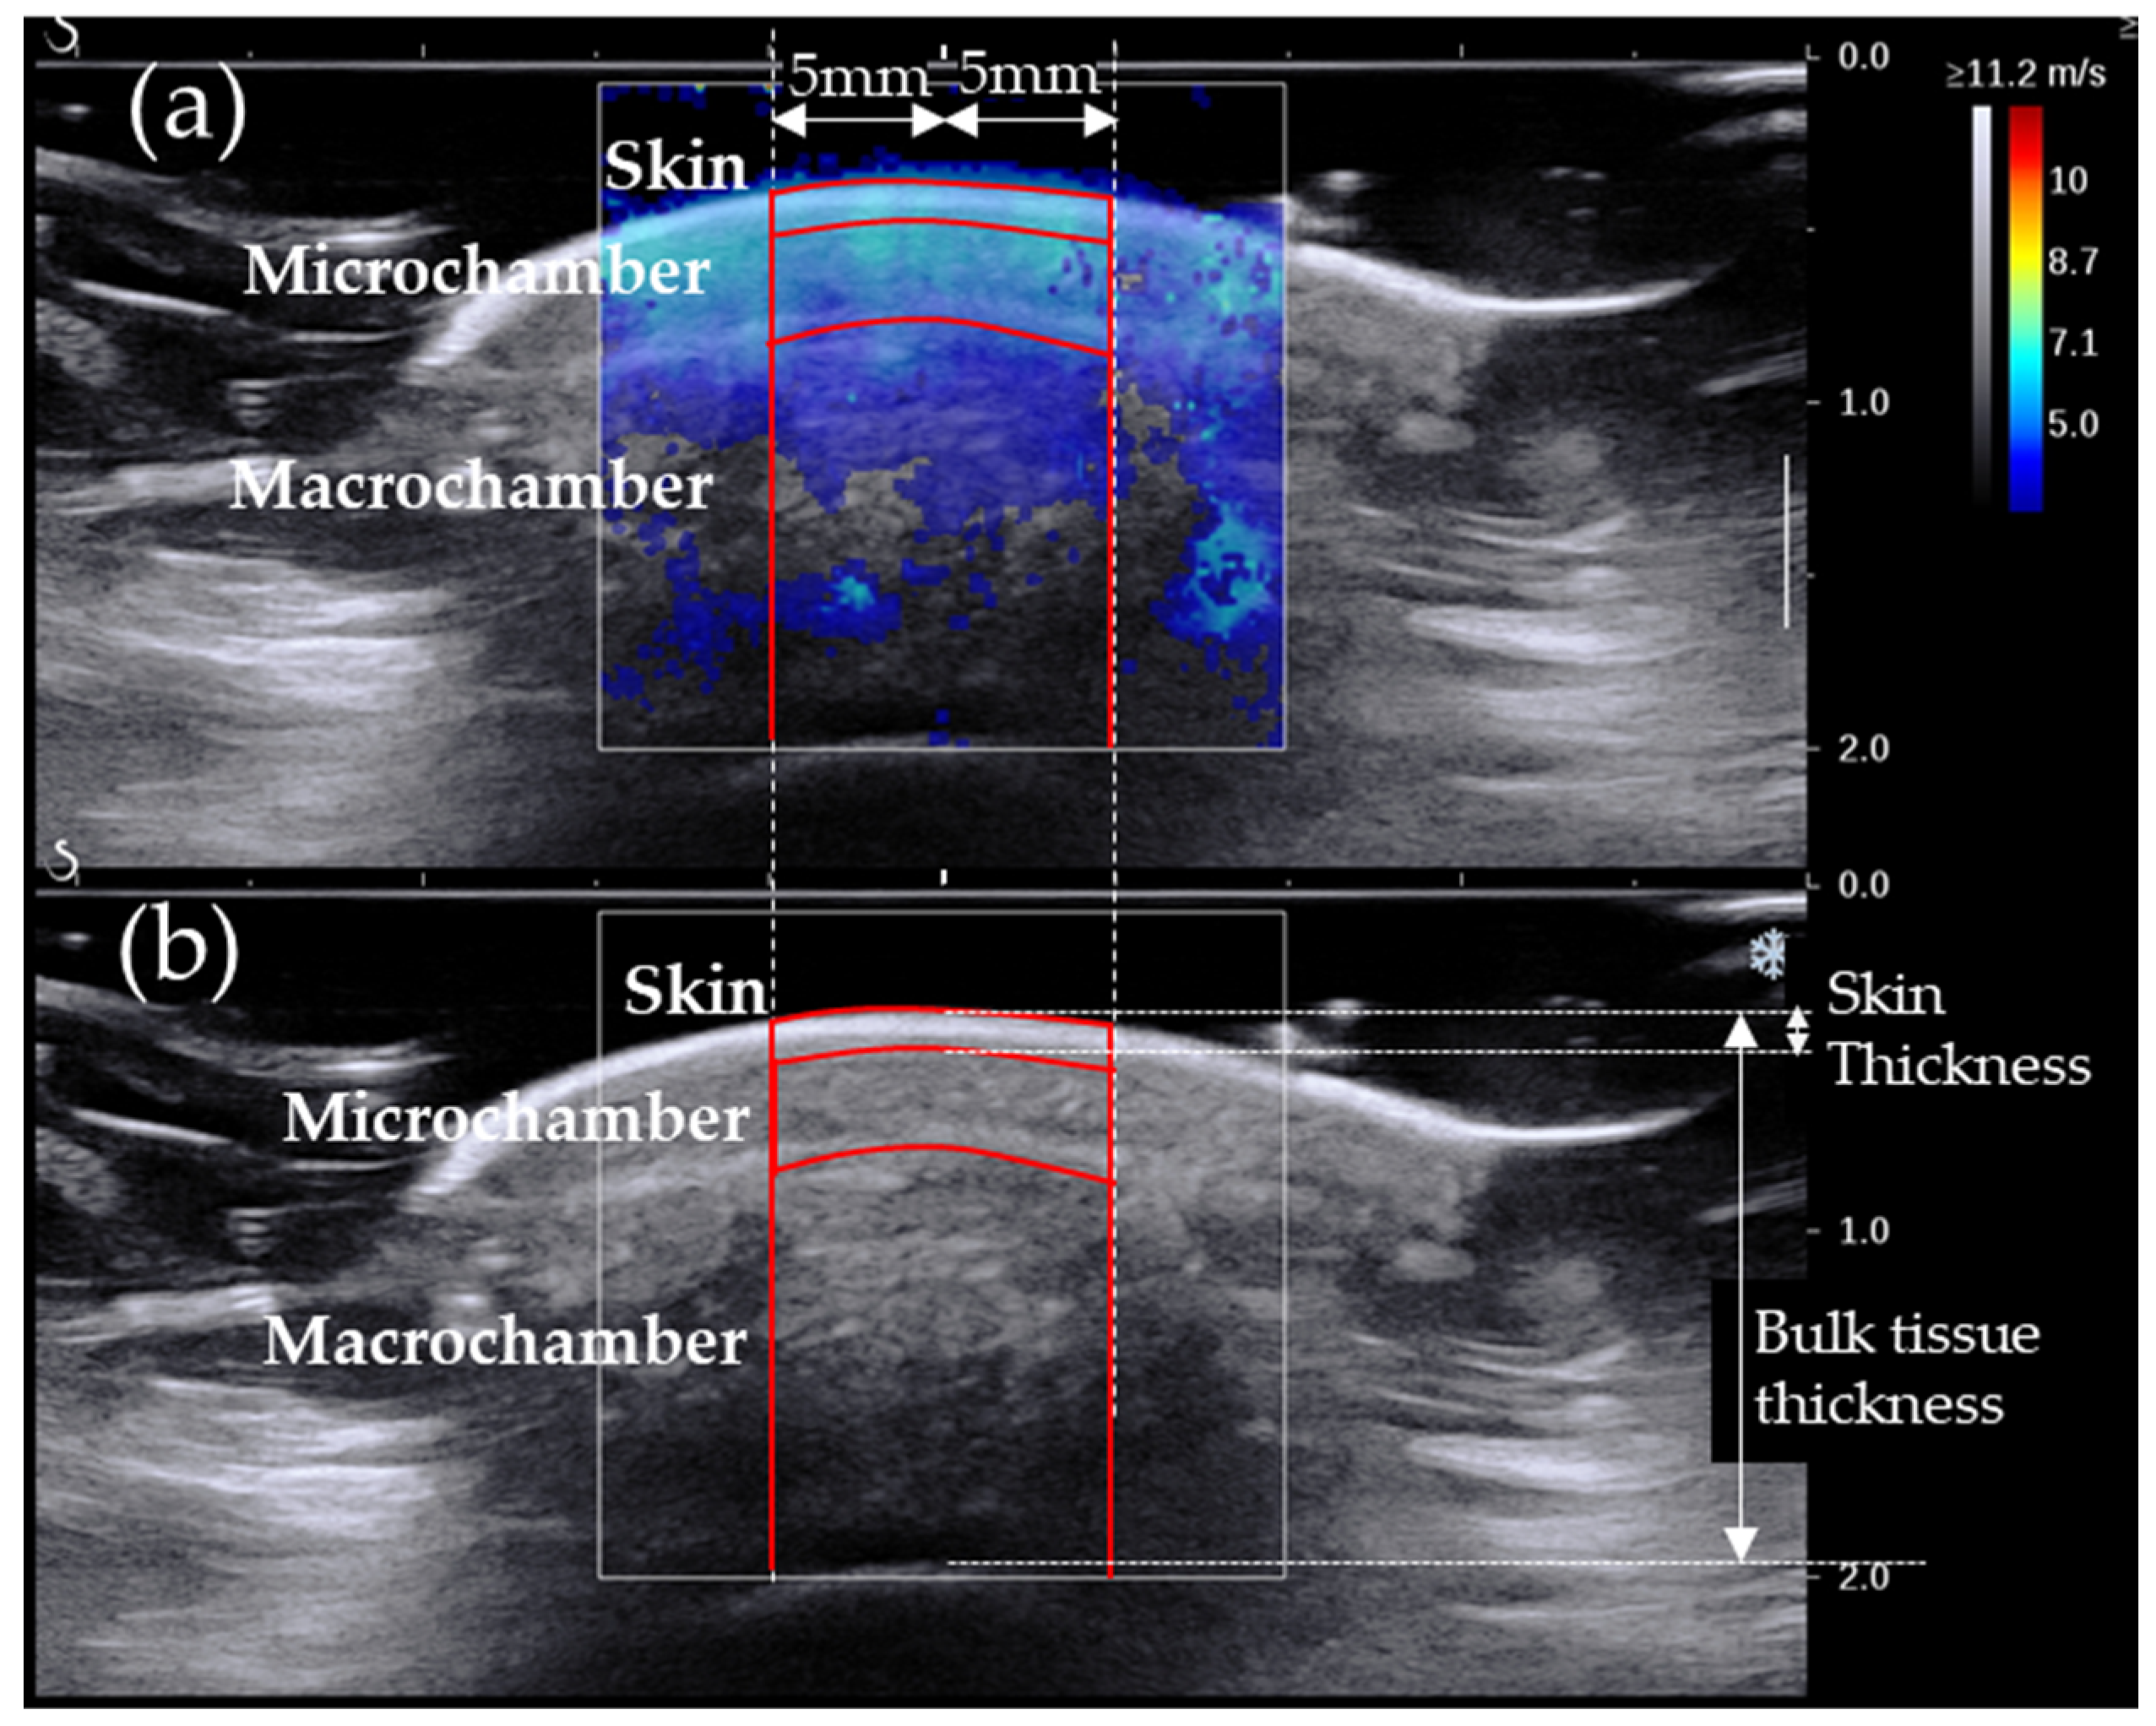

2.2.2. SW Elastography

- Chatzistergos, P.; Behforootan, S.; Allan, D.; Naemi, R.; Chockalingam, N. Shear Wave Elastography Can Assess the In-Vivo Nonlinear Mechanical Behavior of Heel-Pad. J. Biomech. 2018, 28, 114–150. [Google Scholar] [CrossRef] [PubMed]

- Lin, C.Y.; Chen, P.Y.; Shau, Y.W.; Tai, H.C.; Wang, C.L. Spatial-Dependent Mechanical Properties of the Heel Pad by Shear Wave Elastography. J. Biomech. 2017, 53, 191–195. [Google Scholar] [CrossRef] [PubMed]

- Wu, C.H.; Lin, C.Y.; Hsiao, M.Y.; Cheng, Y.H.; Chen, W.S.; Wang, T.G. Altered Stiffness of Microchamber and Macrochamber Layers in the Aged Heel Pad: Shear Wave Ultrasound Elastography Evaluation. J. Formos. Med. Assoc. 2017, 117, 4–9. [Google Scholar] [CrossRef]